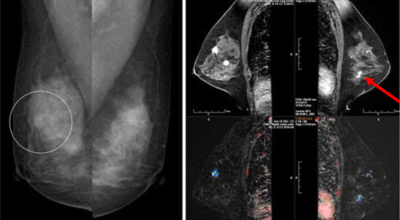

여러 유방암 초기증상들이 있겠지만, 빠른 검사가 필수겠지요. 진단을 위하여 유방촬영술과 초음파를 시행할 수 있다고 해요. 기본으로 시행되는 유방암 검사 중 한가지인 유방촬영술이 있다고 하지만, 한국 여성들은 치밀유방인 경우가 많다고 하지만, 이는 지방조직은 적고 유선조직은 많은 양 있어서 촬영 시에 사진이 하얗게 찍힐 수 있어 혹의 유무를 파악하기가 쉽지 않을 수 있다고 해요.

그리해서 유방암 검사 중 초음파도 병행하게 됩니다. 초음파를 통하여 조직에 생성된 혹의 악성과 양성을 파악하는데 도움을 준다고 해요. 초음파를 진행해도 유방 촬영술 검사는 필요하고, 이유는 미세석회화와 같은 것의 파악은 이 검사로 더욱 잘 관찰될 수 있다고 해요. 이 외 유방암 검사로는 조직검사와 세포침 검사를 통해 병의 상태를 볼 수 있다고 해요.